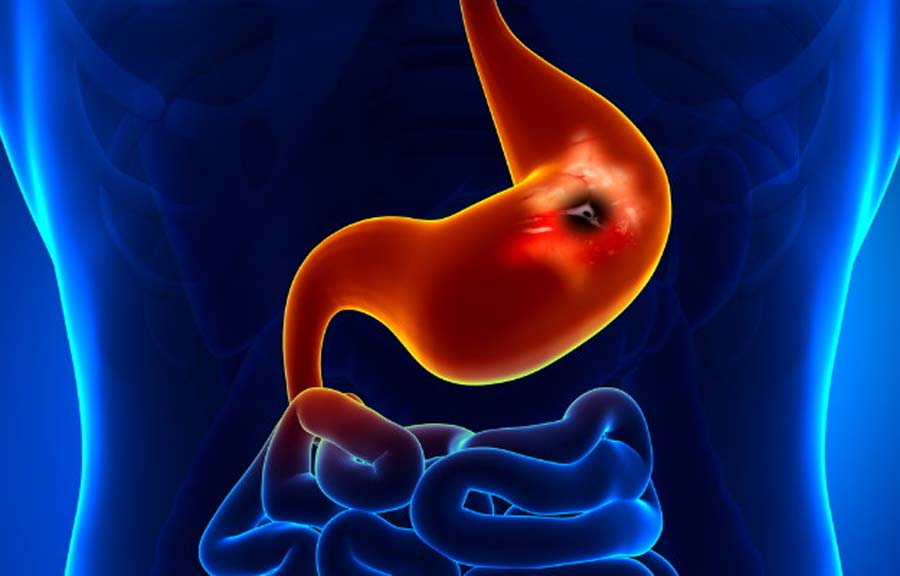

हेल्थ न्युज (एजेंसी)। पेट का अल्सर, जिसे चिकित्सकीय भाषा में गैस्ट्रिक अल्सर भी कहा जाता है, पेट की अंदरूनी परत पर होने वाले घाव होते हैं। यह स्थिति तब उत्पन्न होती है जब पाचन तंत्र में मौजूद एसिड पेट की सुरक्षात्मक दीवार को नुकसान पहुँचाने लगता है। इसके मुख्य कारणों में दर्द निवारक दवाओं का अत्यधिक सेवन या H. Pylori नामक बैक्टीरिया का संक्रमण शामिल हो सकता है।

अल्सर के कारण पेट में जलन, दर्द, सूजन और जी मिचलाने जैसी समस्याएं हो सकती हैं। हालांकि दवाएं अपनी जगह काम करती हैं, लेकिन सही आहार का चुनाव लक्षणों को कम करने और रिकवरी में महत्वपूर्ण भूमिका निभाता है।